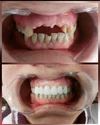

Zirconium Applications

Porcelain Applications

Laminate Veneer